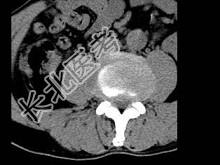

- 单项选择题男,45岁, 腰痛,结合图像, 最可能的诊断是 ( )

A、椎间盘膨出

B、椎间盘突出

C、椎间盘未见异常

D、腰椎骨质增生

E、前纵韧带钙化